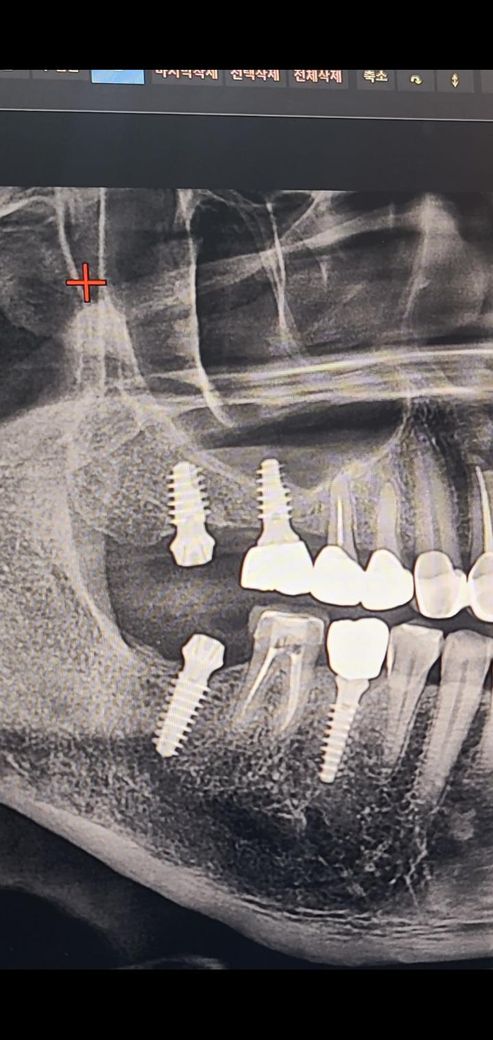

17번 오른쪽 위에 맨 끝부분에 임플란트가 현재 보철이 올라온 상태 인데 씹을때 통증이 있고 오른쪽 편두통 까지 오네요

16번과 17번은 상악동 거상술로 인하여 뼈이식을 같이 한다고 하여 1개 값 50만원을 지불 했었고요, ct 상으로 16번, 17번 임플란트 상악동 뼈이식 수술이 잘되었는지 봐주시길 요망합니다. 현재 17번 제거를 심각하게 고려중이 라서요...

위 파노라마 사진상으론 별다른 문제 없어보입니다 다만 증상이 지속되면 빼는게 수순입니다

사진으로는 #16번부위에 골이식 재료가 보이지는 않습니다. 또한 #17 치아 부위는 치조골이 임플란트 고정체가 들어갈 충분한 양이 있기 때문에 상악동 거상을 하지 않아도 되는 상황으로 보입니다.

임플란트를 하고 통증이 있다면 임플란트가 치조골과 유착이 안됬을수 있습니다. 이런경우에는 재수술이 필요할수 있습니다.